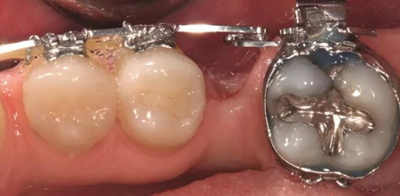

圖2a.病例1中,同期牙槽嵴增量和右下第一磨牙種植位點加速磨牙直立。術(shù)前臨床檢查顯示修復空間小、牙槽嵴吸收

圖2b.增量時,在受區(qū)和右下第二磨牙遠中進行牙槽嵴去皮質(zhì)術(shù)

圖2c. 移植處用膠原膜保護,磨牙后區(qū)用硫酸鈣覆蓋

圖2d. 3個月后,獲得顯著的骨增量,同時創(chuàng)造出1.6mm的近遠中修復空間